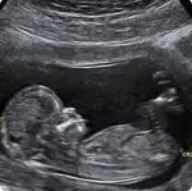

怀孕的准妈妈经常要去做B超,但大多数准妈妈不会看B超单,今天就来教您怎么看B超单上的各种数据。

GS--胎囊,又叫孕囊

月经规则的女性,停经35天,B超就可以看见胎囊。GS的位置在子宫的宫底,前壁,后壁,上部,中部都正常;形态圆形或椭圆形清晰为正常。如果,GS为不规则形,模糊,而且位置在下部,孕妇同时有腹痛或阴道流血,可能会流产。到停经6周,腹部B超仍然看不见GS,不排除宫外孕。

CRL--头臀长

在6-13周之间估计孕龄用头臀长表示。为胎儿头与臀之间的距离,表示胎体纵轴平行测量最大的长轴 ,主要是判定孕7-12周的胎龄。

FH--胎头

轮廓完整为正常,缺损变形为异常 ,脑中线无移位和无脑积水为正常。胎头双顶径的测量是估计胎龄及胎儿成熟度的指标。怀孕26-36周双顶径平均每周增加0.22厘米。怀孕36周后双顶径的增加速度减慢,每周增加0.1厘米。双顶径也可以预测胎儿的体重,如果双顶径达到8.5厘米以上,则胎儿的体重超过2500克。如果,双顶径在9.1-10厘米,新生儿体重在3276-3925克之间。双顶径大于10厘米,新生儿体重在4000克以上。

BDP--胎头双顶径

胎儿头部左右两侧之间最宽的长度,又称【头部大横径】。怀孕足月时应该达到9.3厘米以上。按一般规律,怀孕5个月,基本与怀孕月份相符。也就是说,怀孕7月时,BDP约为7.0厘米,怀孕8月时,BDP约为8.0厘米。如果怀孕初期无法通过CRL来确定预产期时,往往通过BDP来预测。

HR--胎心

B超于怀孕7-8周就可以看见胎心跳动。胎心的跳动,强为正常,弱有二种可能,一是胎儿在睡眠中,二可能为异常。胎心的跳动频率每分钟110-160次之间。

FM--胎动

B超于孕期8-9周就可以看见胎动,有胎动,强为正常, 无胎动,弱,有可能是胎儿在睡觉,也有可能为异常,要结合临床。

PL--胎盘

位置是说明胎盘在子宫壁的位置。正常足月胎盘的厚度应有2.5-5厘米之间。根据绒毛膜,胎盘的光点,基底膜的改变,将胎盘的成熟度分为0,1,2,3级。胎盘的定级表示胎盘的成熟度,正常早期胎盘多为0级,是胎盘的生长阶段。28周后随着胎盘的成熟,由1级向3级发展。

根据以上这些数据,学会并看懂它,准妈妈就可以大致推算出宝宝的发育情况是否良好,是否有异常。